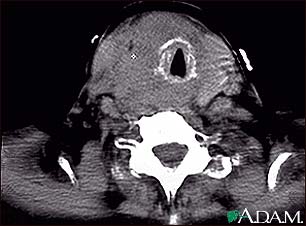

Thyroid cancer - CT scan

This CT scan shows a thyroid cancer tumor in the throat, encircling, narrowing, and displacing the windpipe (trachea).